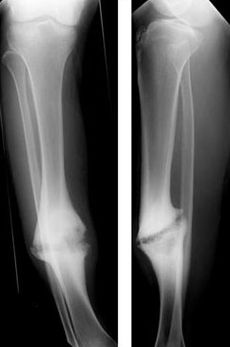

Nonunion.jpg

Hypertrophic nonunion of the tibia

Hypertrophic non-union

Callus is formed, but the bone fractures have not joined. This can be due to inadequate fixation of the fracture, and treated with rigid immobilisation.